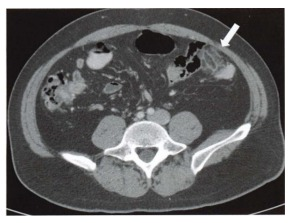

Mulher de 29 anos inicia com dor abdominal aguda em flanco esquerdo. O sintoma é bem localizado e a paciente consegue apontar o local exato da dor. Realizada tomografia com contraste endovenoso que evidencia densificação focal da gordura pericolônica esquerda, na borda antimesentérica, com aspecto em “dedo de luva”, apontado pela seta na figura abaixo. Assinale a alternativa com o diagnóstico CORRETO: